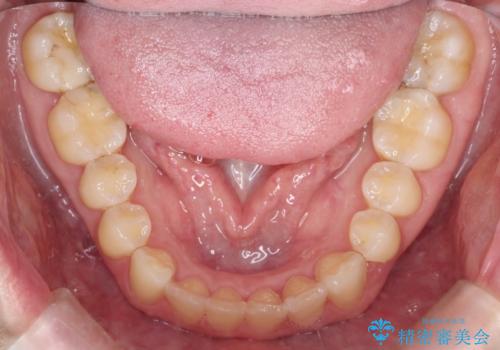

- 前歯の歯並びが気になるとのことで来院されました。

右上の1番目の歯が内側に入り込んでしまっており、その歯がの先端がすり減ってしまっていました。

インビザラインによる矯正治療で前歯の歯並びを改善し、セラミッククラウン装着により歯の形態の回復をする計画としました。